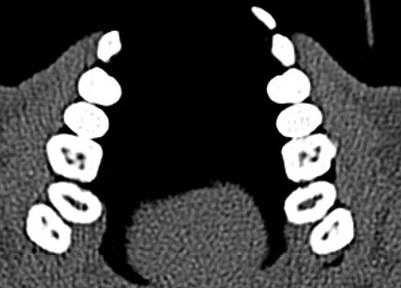

Описаны варианты раздвоения канала нижней челюсти (НЧ), которые были выявлены как случайные находки при конусно-лучевой компьютерной томографии челюстно-лицевой области пациентов, обращавшихся в медицинские центры за стоматологической помощью. Выявленные добавочные каналы в теле НЧ начинались от верхней стенки нижнечелюстного канала и имели небольшую протяженность. Они заканчивались в ретромолярной области, направлялись к корням зубов или ориентировались параллельно основному каналу НЧ.

Удвоение канала нижней челюсти — НЧ (нижнечелюстного канала) — вариант его анатомического строения. О нем имеется упоминание в национальном руководстве по хирургической стоматологии и челюстно-лицевой хирургии [1], а также в ряде научных статей, авторы которых обнаружили дополнительный канал (ы) на анатомических препаратах [2, 3]. Частота выявления нескольких каналов НЧ при анализе ортопантомограмм (ОПМГ) — 0,08—0,95% [4]. Конусно-лучевая компьютерная томография (КЛКТ) выявляет наличие раздвоенного канала в 15,6—64,6% случаев [5—7]. В соответствии с классификацией M. Naitoh и соавт. [5] различают 4 типа канала (рис. 1). Рис. 1. Конфигурация раздвоенного канала НЧ (по M. Naitoh и соавт. [5]). 1-й тип: передний канал — дополнительный канал сливается с основным (а) или оба они идут параллельно (б); 2-й: щечно-язычный канал — расположен со щечной (в) или язычной (г) стороны от основного канала; 3-й: дентальный канал — ведет к корням зубов (д); 4-й: ретромолярный канал — заканчивается ретромолярным отверстием в одноименной ямке (е).

Рентгенологическое исследование проводилось на аппарате Galileos GAX5 («Sirona Dental Systems, Bensheim», Germany). Анализ полученных данных проводился по традиционной методике, предусматривающей последовательное изучение сначала срезов в 3 взаимно перпендикулярных проекциях (окно мультипланарной реконструкции), затем срезов, расположенных продольно и поперечно относительно зубной дуги (в окне «Панорама»), а также томограмм произвольной кросс-секции, оптимальной для получения изображений анатомических объектов соответственно их пространственному положению. Оптимальными для визуализации вариантов ветвления канала НЧ являлись реформаты вдоль продольной оси ее тела, которые обозначаются по терминологии разработчиков аппарата как «касательные».

Ниже представлены описания рентгенологической картины раздвоенного канала НЧ 3 типов.

Пациентка Е., 48 лет. С левой стороны на уровне угла НЧ от нижнечелюстного канала отходила боковая ветвь (рис. 2). Рис. 2. Ретромолярный канал; КЛКТ пациентки Е., 48 лет. 1 — канал НЧ; 2 — ретромолярный канал; 3 — подбородочное отверстие. Ее поперечный диаметр составлял 1,37 мм у места начала и 0,96 мм в области ретромолярного отверстия.

Поперечный диаметр канала НЧ у места начала ветви — 3,08 мм. Сначала дополнительный канал направлялся вперед. На расстоянии 5,33 мм от места бифуркации он образовывал петлю, менял направления хода и шел назад и вверх, заканчиваясь отверстием в ретромолярной области. Описанный ход характерен для ретромолярного канала (4-й тип раздвоенного канала НЧ). На контралатеральной стороне дополнительных каналов НЧ не обнаружено.

Пациентка Ф., 55 лет. С правой стороны на уровне угла челюсти от верхней стенки нижнечелюстного канала начинался дополнительный канал с поперечным диаметром 1,52 мм (рис. 3, а). Рис. 3. Дентальный канал нижней челюсти. а — КЛКТ пациентки Ф., 55 лет; б — КЛКТ пациентки К., 29 лет. 1 — канал НЧ; 2 — дентальный канал; 3 — подбородочное отверстие. Поперечный диаметр основного канала на этом же уровне — 2,70 мм. Дополнительный канал направлялся полого вперед и вниз параллельно основному каналу НЧ. В мезиальном направлении кортикализация стенок дополнительного канала постепенно уменьшалась, и достоверно проследить его ход удалось до уровня зуба 4.7. Описанная картина характерна для дентального канала (3-й тип раздвоенного канала НЧ). С левой стороны визуализация дополнительного канала была недостоверной: выявлялось линейное просветление такой же локализации и направления, как с правой стороны, но картины трубчатого образования не выявлено, вероятнее всего — вследствие недостаточной кортикализации его стенок.

У пациентки К., 29 лет, с левой стороны обнаружен дентальный канал (см. рис. 3, б). В месте отхождения он имел вертикальный диаметр 1,35 мм (приблизительно в 3 раза меньше вертикального диаметра канала НЧ на этом же уровне), направлялся вперед и вниз, располагаясь параллельно основному нижнечелюстному каналу, и на уровне медиального корня зуба 3.7 круто поднимался вверх. Дентальный канал переставал идентифицироваться на уровне средней трети корня второго нижнего левого моляра. С правой стороны раздвоения канала НЧ не выявлено.

Пациентка Б., 57 лет. С правой стороны на уровне угла НЧ определялась добавочная ветвь нижнечелюстного канала диаметром 1,1 мм, которая, начинаясь от его верхнего контура, далее шла вперед почти параллельно основному каналу на протяжении 8,01 мм, а затем сливалась с ним (рис. 5). Рис. 5. Конфигурация канала НЧ; КЛКТ пациентки Б., 57 лет. 1 — канал НЧ; 2 — передний канал. На контралатеральной стороне добавочных каналов не обнаружено. Описанная рентгенологическая картина соответствует 1-му (а) типу раздвоенного канала НЧ.

Канал НЧ при типичной локализации визуализируется в виде трубчатого костного образования, стенки которого представлены тонкими линейными затемнениями кортикальных пластинок, а содержимое канала отображается в виде интенсивного просветления. Калибр канала постепенно уменьшается в мезиальном направлении. Достоверным признаком наличия дополнительного канала является продолжение в его стенку кортикальной пластинки основного канала. Это дает возможность проследить дополнительный канал на всем его протяжении. У места его начала канал НЧ, как правило, имеет локальное расширение. Дополнительные каналы обычно отходят от верхней стенки канала НЧ и имеют небольшую протяженность.